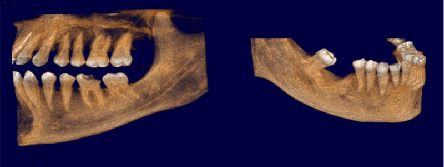

Pro Patient: Our state-of-the-art cone-beam computed tomography (CBCT) technology could selectively image the sinus, oral maxillofacial, para-nasal sinuses, ear & throat regions.

3D Imaging with Field of View sizes available in:

Proactive Dental Management thru our 3D Imaging Manipulation Software

With Oral Maxillofacial CT Scans, your dentist enhances his ability to proactively manage your health concern thru accurate diagnosis & better treatment planning. Moreover, the patient benefits from a painless,low radiation dose CT Scan procedure.